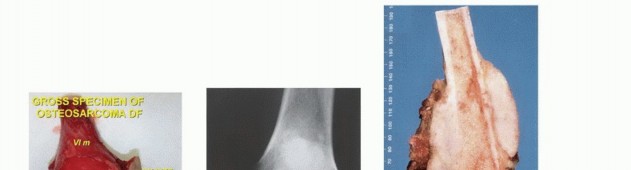

Sarcomas originate primarily from the embryonic mesoderm. Soft tissue sarcomas are broadly classified based on the mature tissue they most closely resemble histologically (e.g., liposarcoma resembles adipose tissue, leiomyosarcoma resembles smooth muscle). Bone sarcomas are classified by the dominant extracellular matrix produced by the malignant cells: osteoid-producing tumors are osteosarcomas, while chondroid-producing tumors are chondrosarcomas.

Histologic grading is the most critical prognostic indicator for sarcomas. Tumors are graded as low, intermediate, or high grade. The assignment of grade depends on a composite assessment of tumor morphology, cellular pleomorphism, nuclear atypia, matrix production, and most importantly, mitotic index and the presence of spontaneous tumor necrosis.

Tumor grade directly reflects the biologic aggressiveness and the statistical probability of systemic metastasis. Low-grade lesions are locally aggressive but rarely metastasize. High-grade lesions possess a high metastatic potential, disseminating in over 20% of patients, and often present with occult micrometastases.